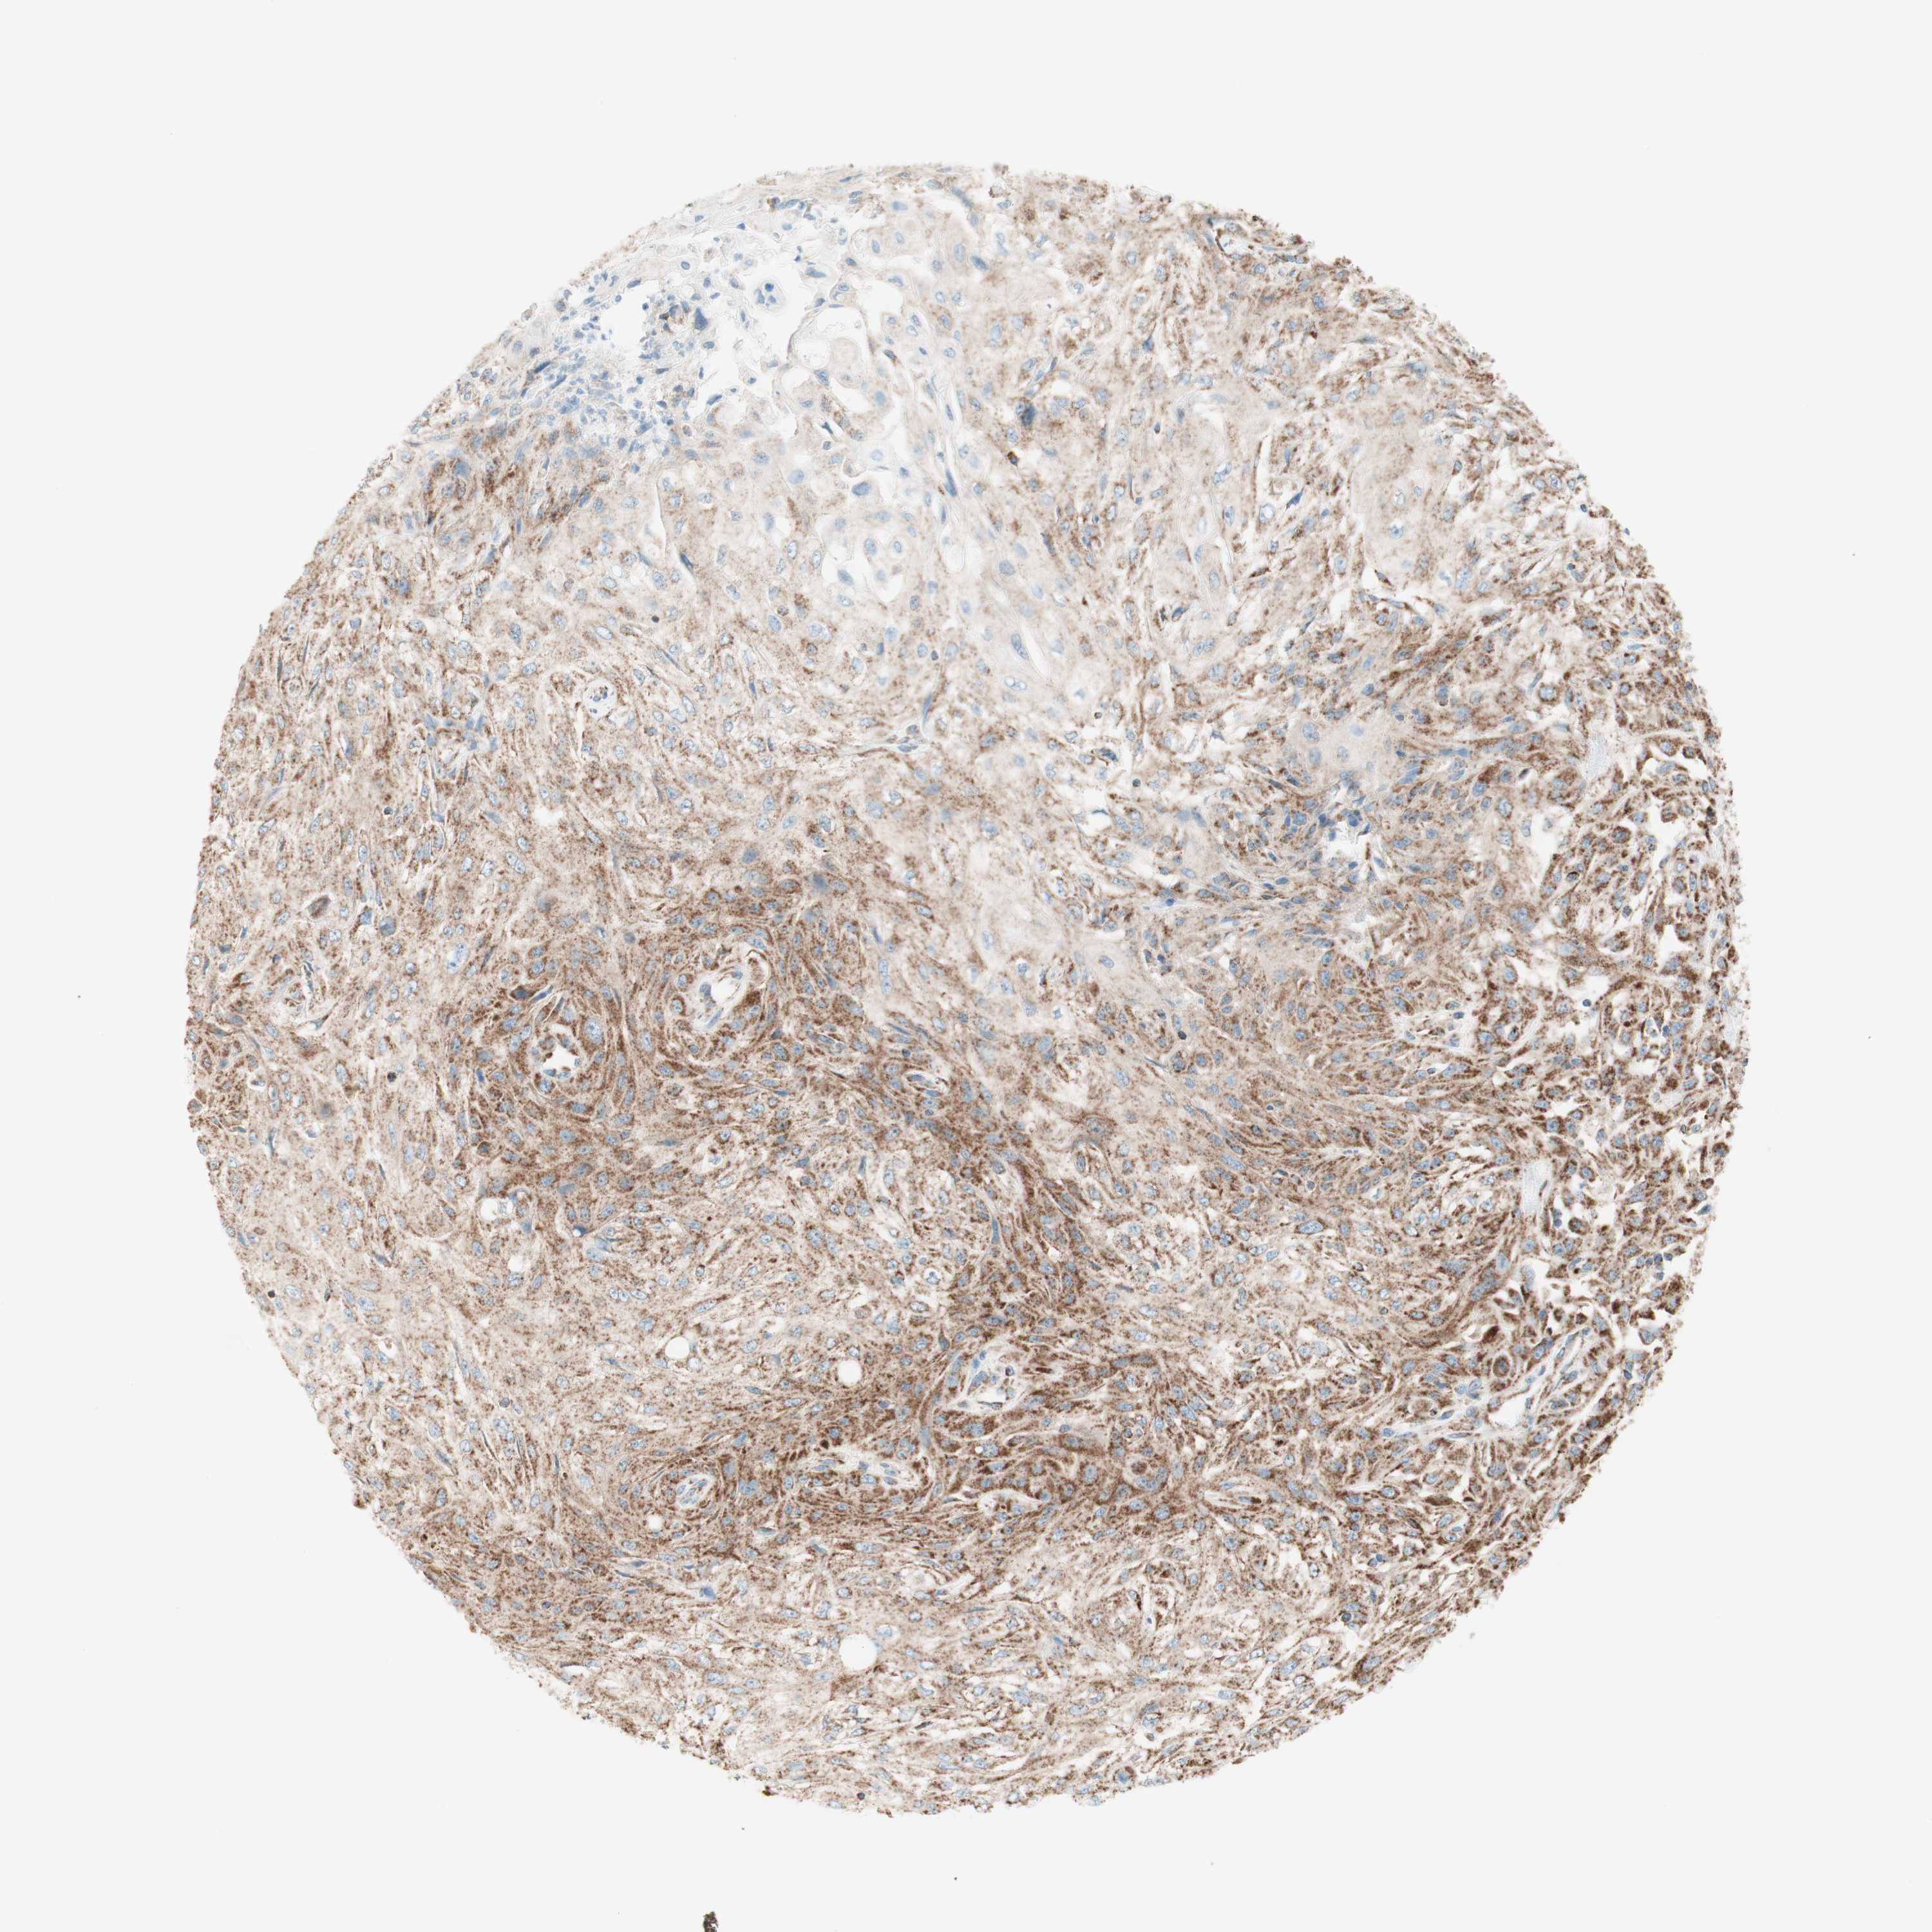

SKIN CANCER - Protein expressioni

A mouse-over function shows sample information and annotation data. Click on an image to view it in a full screen mode. Samples can be filtered based on level of antibody staining by selecting one or several of the following categories: high, medium, low and not detected. The assay and annotation is described here.

Antibody stainingi

Antibody staining in the annotated cell types in the current human tissue is reported as not detected, low, medium, or high, based on conventional immunohistochemistry profiling in selected tissues. This score is based on the combination of the staining intensity and fraction of stained cells.

Each image is clickable and will lead to virtual microscopy that enables deeper exploration of all samples and also displays staining intensity scores, fraction scores and subcellular localization as well as patient and tissue information for each sample.

Antibody CAB005585

Squamous cell carcinoma, NOS

Basal cell carcinoma

Squamous cell carcinoma, metastatic, NOS